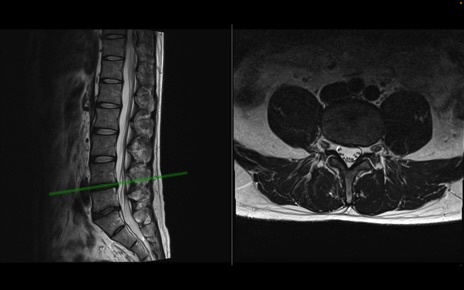

【整形】TIPS症例1 腰椎MRI 横断像と矢状断像

【症例】40歳代男性

【主訴】左臀部〜大腿後面痛み

【現病歴】2週間前から腰痛あり。2日前に夜中にくしゃみをした際に激痛が出現。疼痛強いため来院。

【身体所見】左臀部〜大腿後面、下腿後面のしびれ。SLR -/+ 30度、うつ伏せ困難、筋力低下なし。

異常所見と診断は?